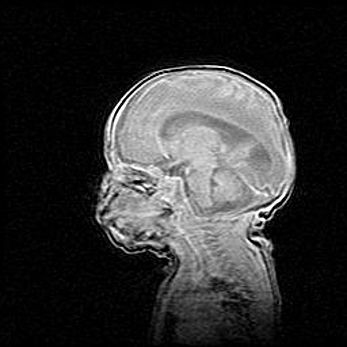

Церебральная ишемия II.

Возраст: 5 дней

Вес: 3400 г

Пол: женский

Окружность головы: 35 см

Срок гестации: 39 недель

Церебральная ишемия – это заболевание, характеризующееся недостаточностью (гипоксией) либо полным прекращением (аноксией) снабжения мозга кислородом по причине закупорки одного или нескольких сосудов. Это приводит к  что метаболическим расстройствам различной степени тяжести в тканях головного мозга, развитию коагуляционных некрозов и гибели нейронов.